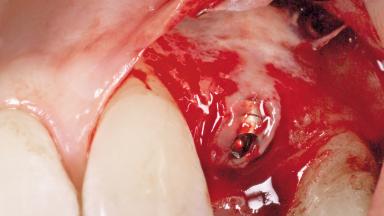

A 51-year-old female patient presented with a chief complaint of occlusal pain at tooth 24 and had been referred to our clinic for consultation and treatment. The patient had no history of any systemic disorder that may have affected the treatment outcome, and she was a non-smoker. Tooth 24 had been endodontically treated and restored with a crown at another clinic due to caries ten years before. The pre-treatment radiograph revealed a root fracture of tooth 24 with significant bone resorption. The pocket probing depth was 8 mm. The tooth had to be extracted. During the minimally traumatic extraction of tooth 24, a dehiscence was found on the buccal wall of the extraction socket. In response to the patient’s wish for a comprehensive treatment of the entire jaw,a suitable treatment plan was developed.